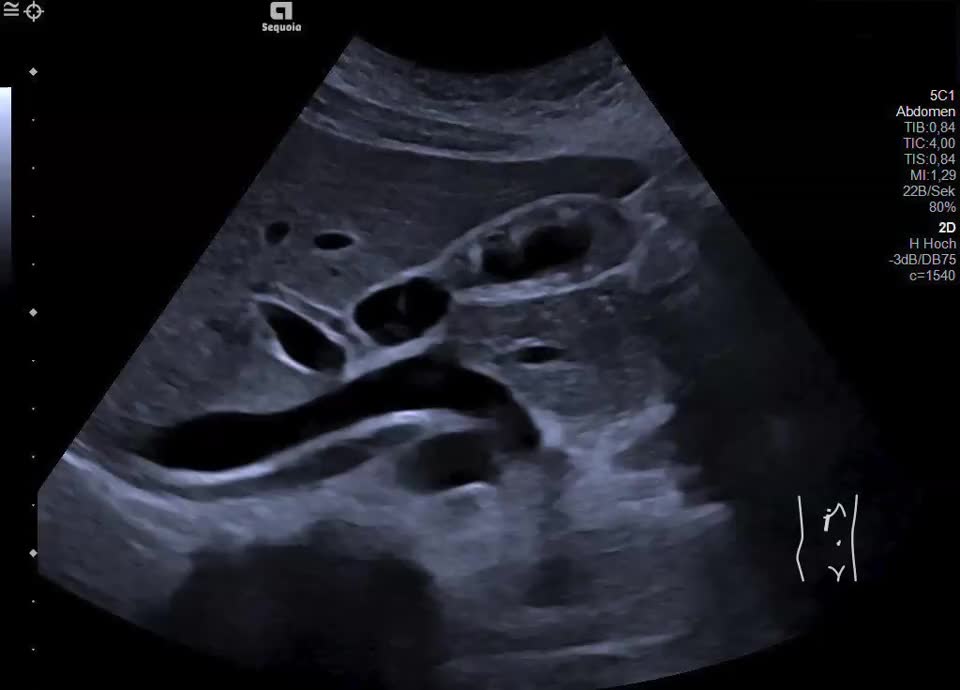

16-jährige Patientin berichtet seit mehreren Monaten über rezidivierende Durchfälle und Bauchschmerzen im Bereich der rechten Colonflexur, zuletzt etwa alle 14 Tage. Vor zwei Monaten wurde sie nach einer besonders starken Episode in die Klinik überwiesen; Labor unauffällig. Zum Zeitpunkt der letzten Untersuchung beschwerdefrei. Sonographisch zeigt sich eine Wandverdickung der Gallenblase mit inhomogener Schichtung bei erhaltener, glatter Innen- und Außenkontur. Betroffen sind vor allem Fundus und Corpus, das Infundibulum erscheint unauffällig. In den verdickten Wandabschnitten finden sich hyperechogene Einzelechos mit Reverberationsartefakten (Kometenschweifartefakte). Zusätzlich zeigen sich in der Hochfrequenzsonografie (Video) echofreie, kleinzystische Areale in der Wand, die den erweiterten Rokitansky-Aschoff Sinus entsprechen. Charakteristischer Befund einer segmentalen Gallenblasenadenomyomatose.